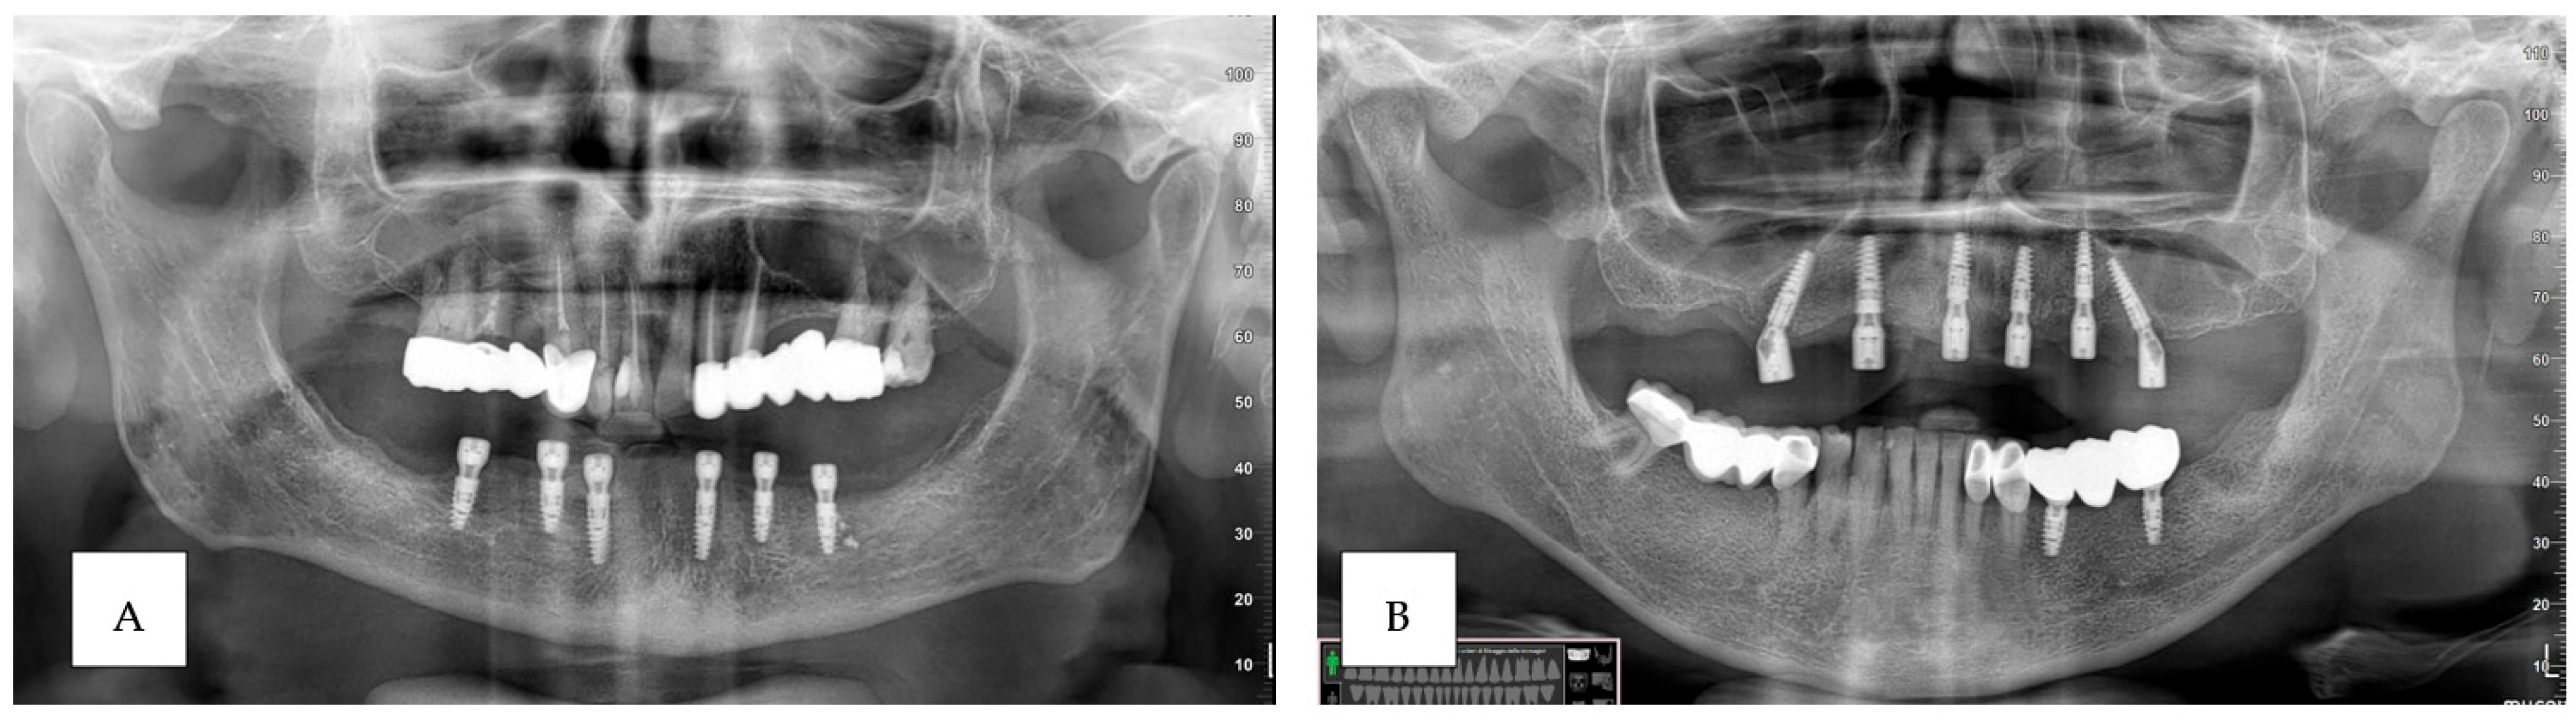

3. Results